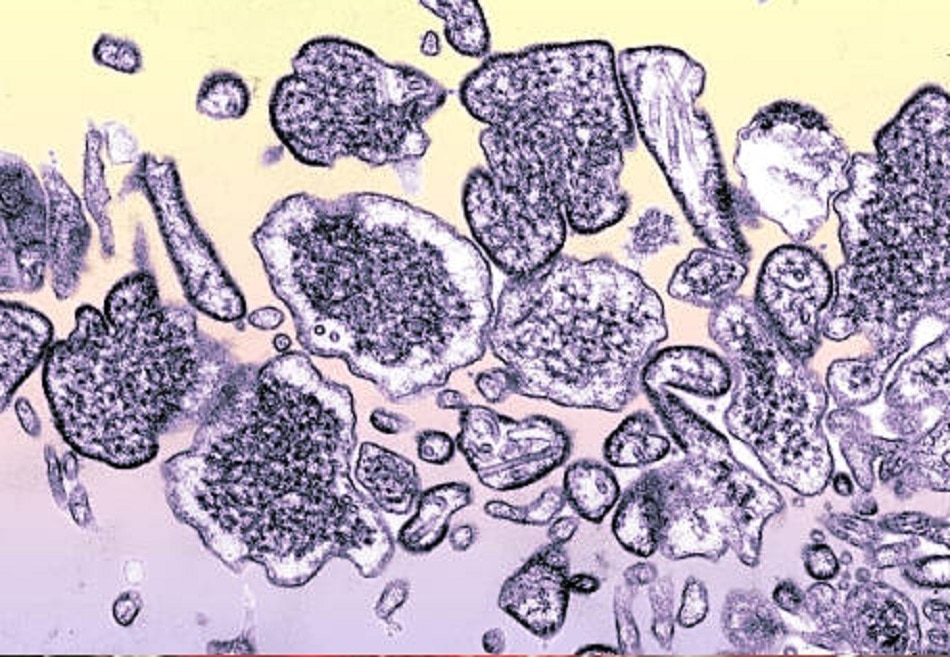

Nipah Virus: निपाह वायरस के ये लक्षण दिखते ही तुरंत हो जाएं सावधान, जानें बचाव के भी तरीके

WHO (विश्व स्वास्थ संगठन) के मुताबिक, निपाह वायरस इंसानों में एसिम्प्टोमैटिक इंफेक्शन से लेकर एक्यूट रेस्पिरेटरी इंफेक्शन और घातक इन्सेफलाइटिस का खतरा पैदा करता है. यह बीमारी जानवरों से इंसानों के बीच फैलती है. निपाह वायरस चमगादड़ और सूअर से इंसानों में फैल सकता है. संक्रमित व्यक्ति के संपर्क में आकर दूसरे लोग भी बीमारी का शिकार हो सकते हैं.